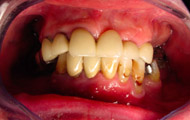

Exemple de 3 dents manquantes remplacées par 3 couronnes sur implants.

Pose des piliers prothétiques et des 3 couronnes scellées.

Exemple d’une réhabilitation complète implantaire

Situation clinique initiale

Situation clinique terminée